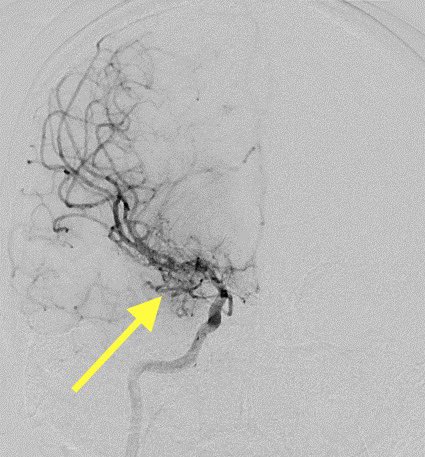

Imaging of Moyamoya disease/syndrome Imaging: Thread-like intracranial ICA/MCA with attenuated branches and “puff of smoke” appearance on DSA Co